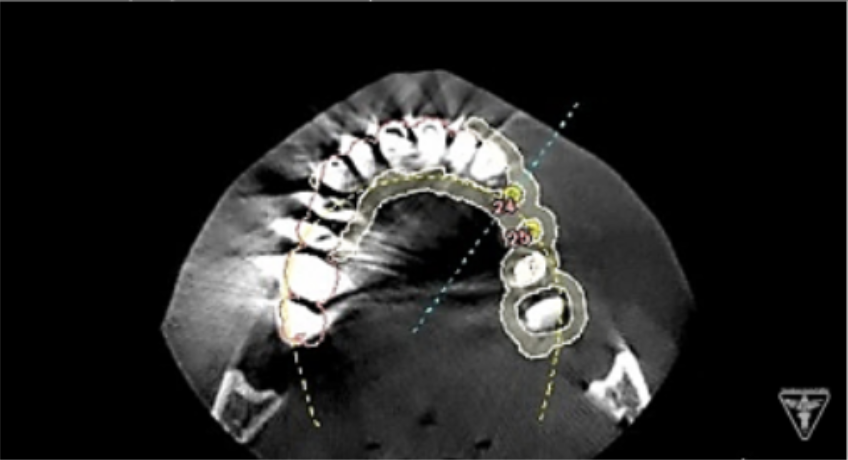

インプラント埋入前のCTによる確認